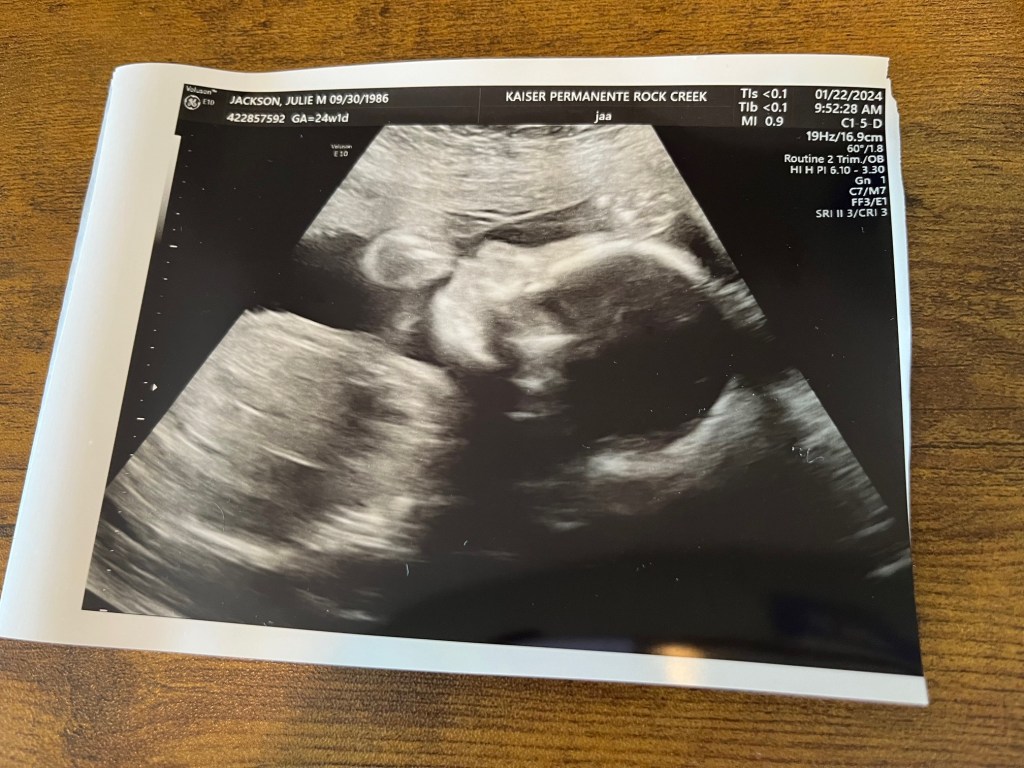

Since this meant seeing Rowan on the same 3D ultrasound machine used in our anatomy scan, I had no objections.

The day of the EKG arrived, and everything was looking good, as usual. Also as usual, Rowan was being a little difficult for the ultrasound tech. He was in a position where some of the measurements they needed couldn’t be taken.

All in all, Rowan’s little ticker is looking just fine, and there are no major concerns. And, as usual, we got another great pic of our little boy to take home! He’s going to have quite the scrapbook even before he’s born!